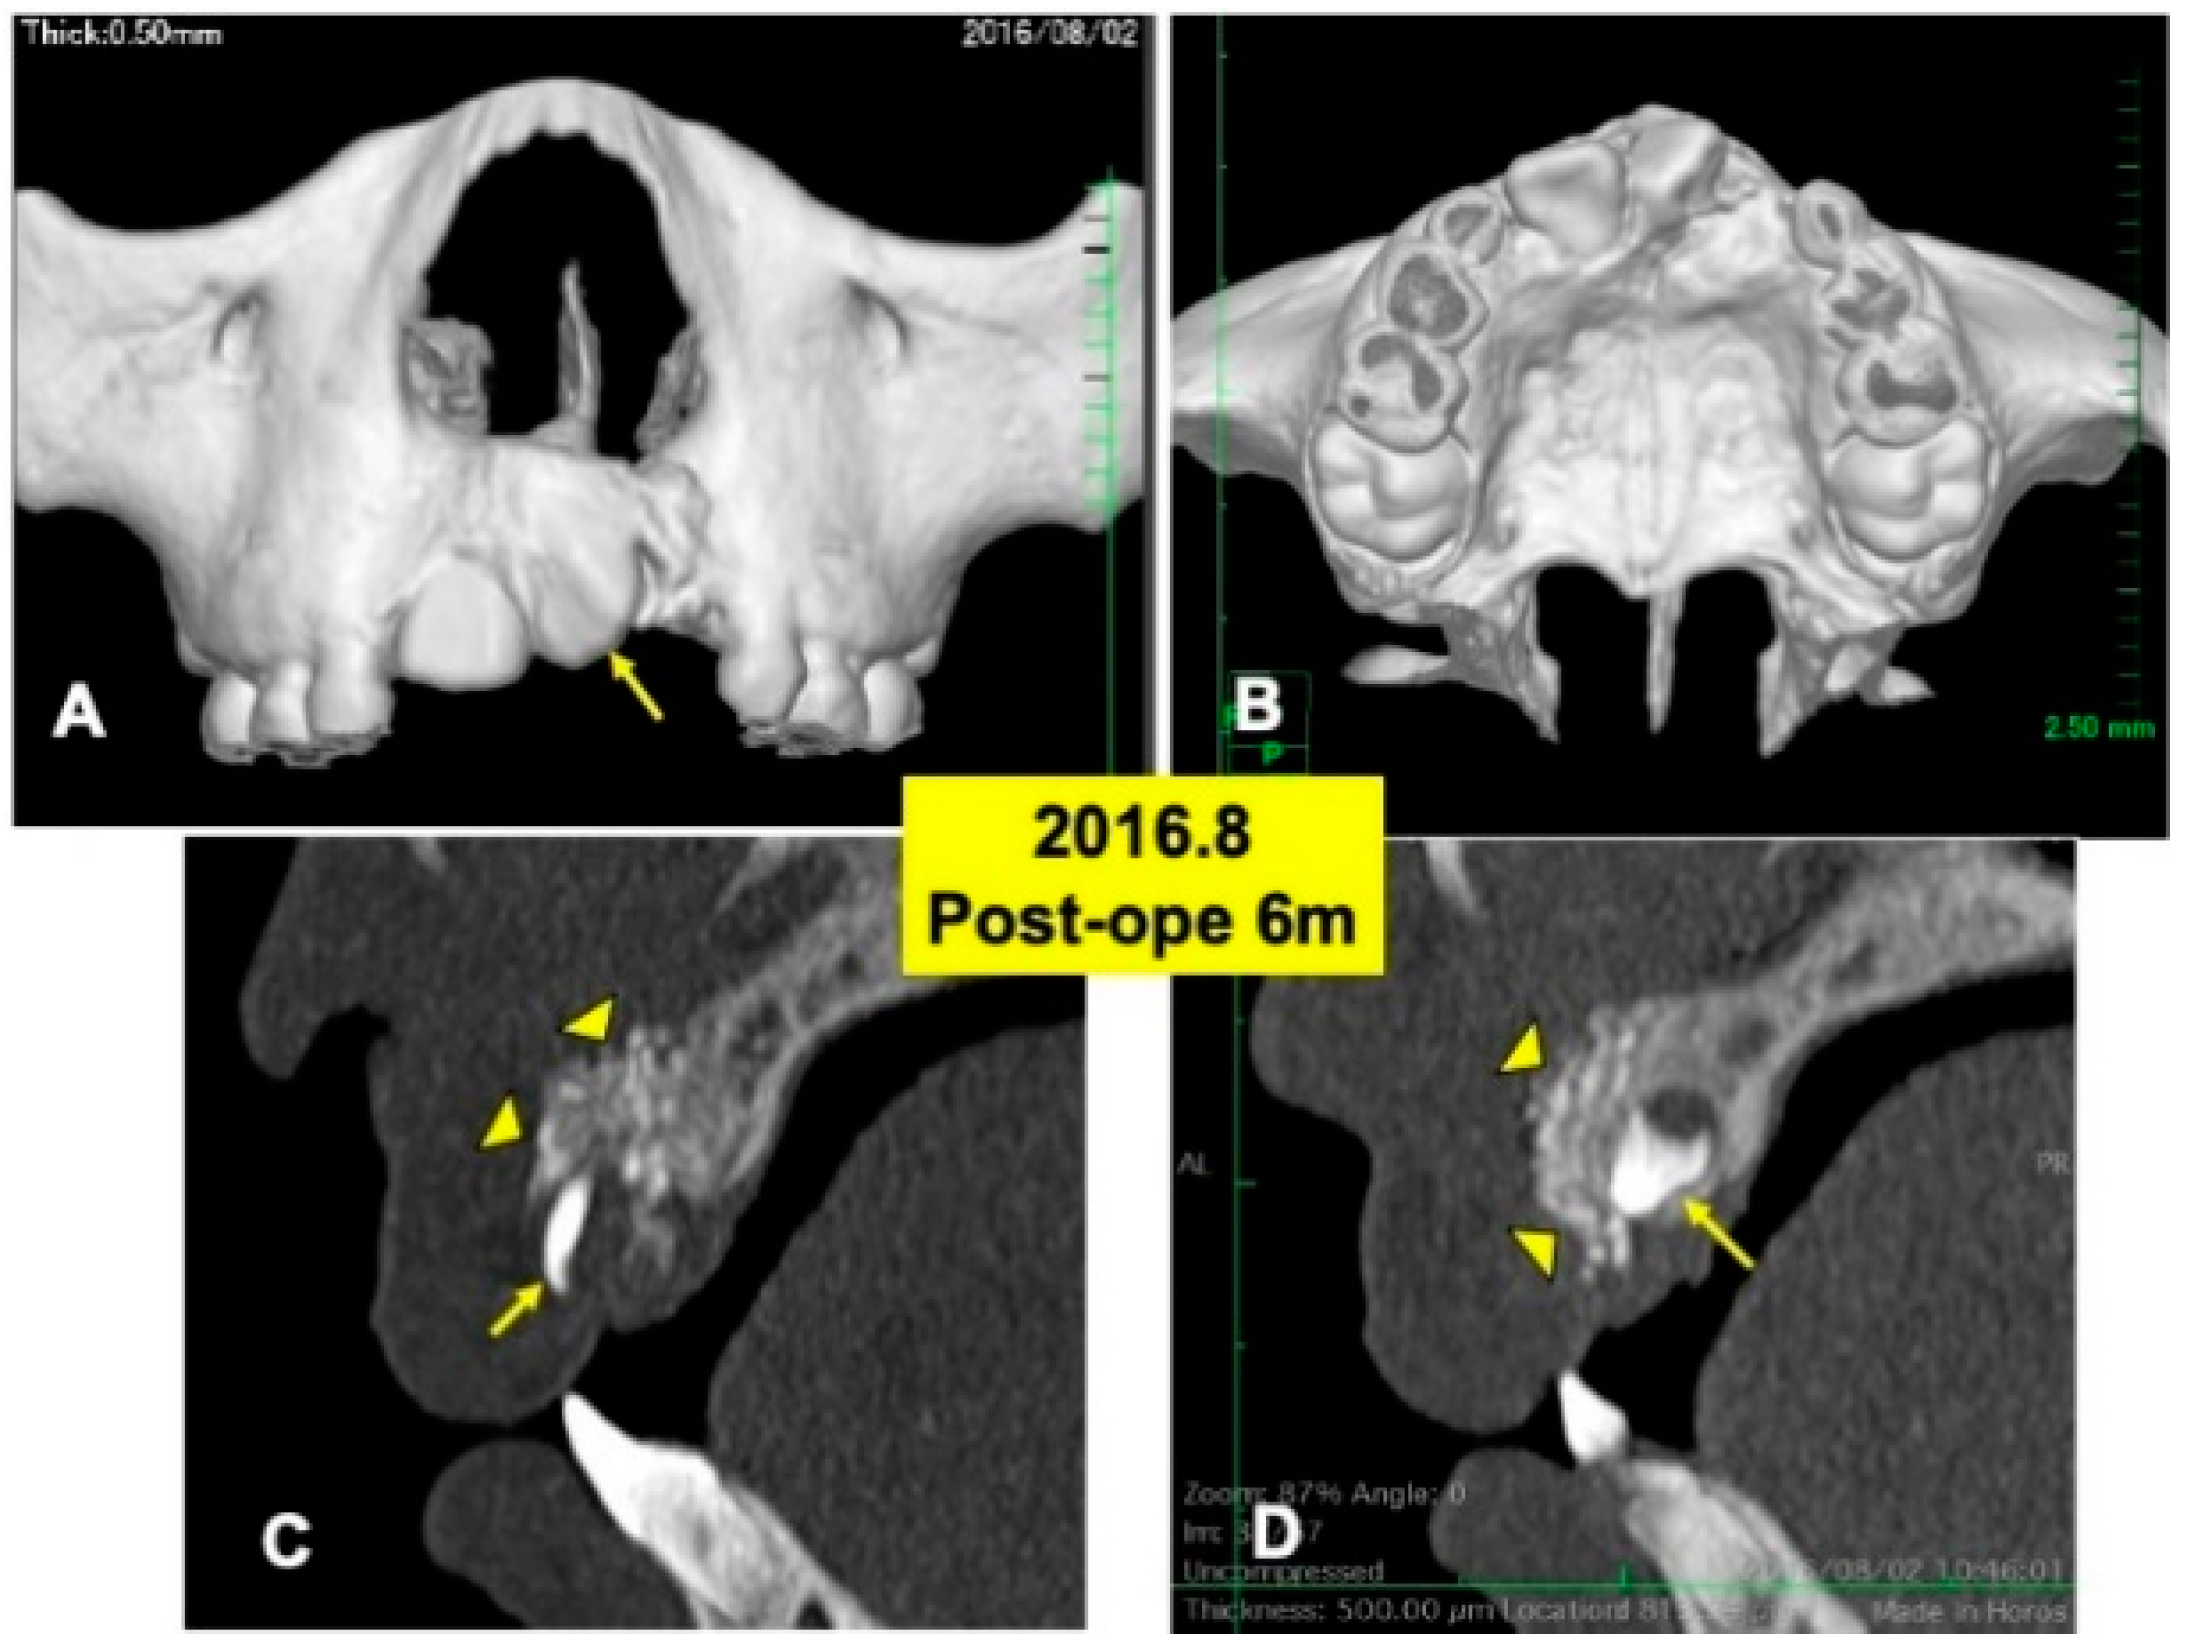

Figure 4.

X-ray CT photos at 6 months after surgery. (A) Labial view of 3D-CT showing continuous hard tissues in cleft area. Arrow indicating rotation of tooth 21. (B) Palatal view of 3D-CT. (C) DDM granules (arrowheads) in cleft near incisor (22: arrow). (D) DDM granules (arrowheads) on impacted canine (23: arrow).

One day after the surgery, a blood clot was formed in the extracted sockets. Mucosa inflammation at the recipient site was slight, and wound healing proceeded normally. The maxillary splint was removed at 7 days. The grafted DDM granules were not exposed. X-ray CT photos were taken at 6 months after the DDM graft (Figure 4), 2 years (Figure 5) and 4 years (Figure 6). During the whole follow-up period for 6 years, complications did not occur. In the CT images at 6 months, a continuous contour of maxilla was observed (Figure 4A,B). The grafted DDM were confirmed near teeth (22,23) as radiopaque granules and could be distinguished from the original bone by the structure and the radio-opacity (Figure 4C,D).